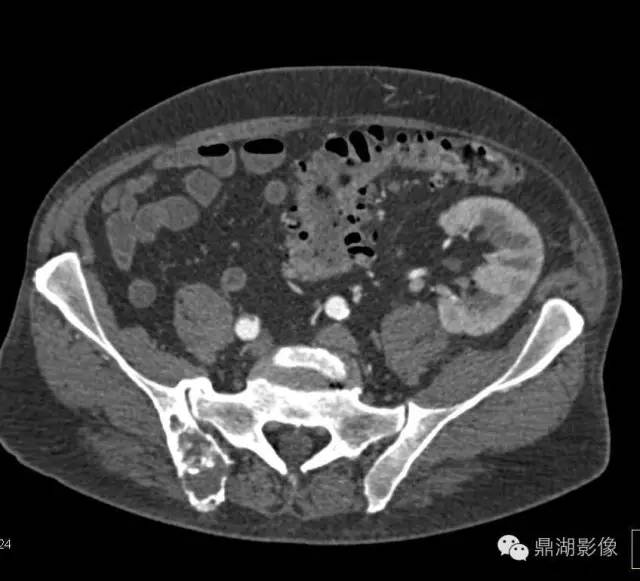

肾细胞癌骨转移

(六)肾癌骨转移 约23.5%发生骨转移,多见于股骨、肱骨、脊柱、骨盆、肋骨等处。常为单发,溶骨性破坏,骨干稍有膨胀,可侵蚀破坏骨皮质,发生病理性骨折。骨缺损区内有骨性间隔出现,颇似原发性肾肿瘤。也可为硬化型,或有广泛多层骨膜反应。